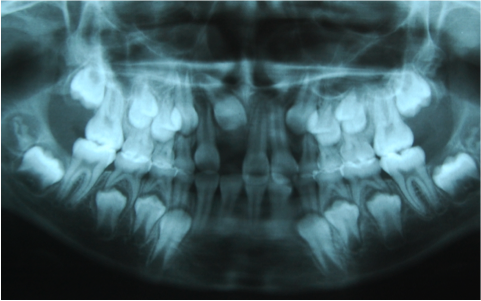

Traccion de un diente retenido